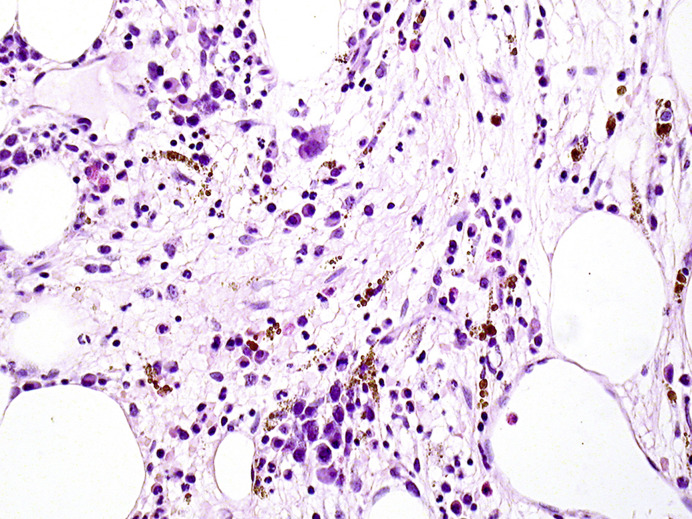

Disease progression in myelodysplastic syndromes (MDS), myelodysplastic-myeloproliferative neoplasms (MDS/MPN), and myeloproliferative neoplasms (MPN), altogether referred to as myeloid neoplasms (MN), is a major source of mortality. Apart from transformation to acute myeloid leukemia, the clinical progression of MN is mostly due to the overgrowth of pre-existing hematopoiesis by the MN without an additional transforming event. Still, MN may evolve along other recurrent yet less well-known scenarios: (1) acquisition of MPN features in MDS or (2) MDS features in MPN, (3) progressive myelofibrosis (MF), (4) acquisition of chronic myelomonocytic leukemia (CMML)-like characteristics in MPN or MDS, (5) development of myeloid sarcoma (MS), (6) lymphoblastic (LB) transformation, (7) histiocytic/dendritic outgrowths. These MN-transformation types exhibit a propensity for extramedullary sites (e.g., skin, lymph nodes, liver), highlighting the importance of lesional biopsies in diagnosis. Gain of distinct mutations/mutational patterns seems to be causative or at least accompanying several of the above-mentioned scenarios. MDS developing MPN features often acquire MPN driver mutations (usually JAK2), and MF. Conversely, MPN gaining MDS features develop, e.g., ASXL1, IDH1/2, SF3B1, and/or SRSF2 mutations. Mutations of RAS-genes are often detected in CMML-like MPN progression. MS ex MN is characterized by complex karyotypes, FLT3 and/or NPM1 mutations, and often monoblastic phenotype. MN with LB transformation is associated with secondary genetic events linked to lineage reprogramming leading to the deregulation of ETV6, IKZF1, PAX5, PU.1, and RUNX1. Finally, the acquisition of MAPK-pathway gene mutations may shape MN toward histiocytic differentiation. Awareness of all these less well-known MN-progression types is important to guide optimal individual patient management.